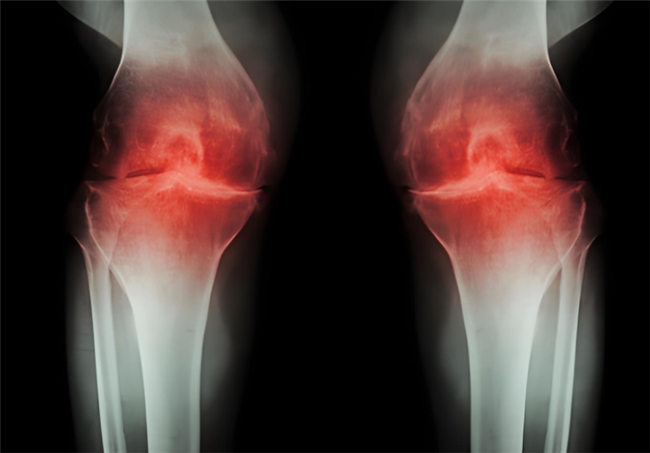

数九寒冬,不少人的关节也在经历“酷刑”——膝盖酸痛、僵硬发麻,上下楼时还会发出“咔咔”的声响,严重时甚至行走都成问题。这往往是骨关节炎在作祟。这个潜伏在体内的“关节杀手”,常在寒冷刺激、关节负重等情况下加重。骨关节炎的核心问题在于关节软骨的磨损,氨基葡萄糖是临床常用的治疗药物之一。然而氨基葡萄糖又分为盐酸和硫酸两种类型,很多人并不清楚:两者作用有何区别?市面上常见的硫酸氨基葡萄糖胶囊功效会更好吗?该如何选择才能有效守护关节健康?

盐酸和硫酸氨基葡萄糖胶囊都是氨基葡萄糖类药物,能为关节软骨提供合成原料,在促进软骨基质的修复与再生的基础上,补充关节滑液以减少摩擦,同时通过抑制关节腔内的炎症因子,从多个方面帮助延缓骨关节炎的进展[1],但它们在临床疗效上却存在一定差异。